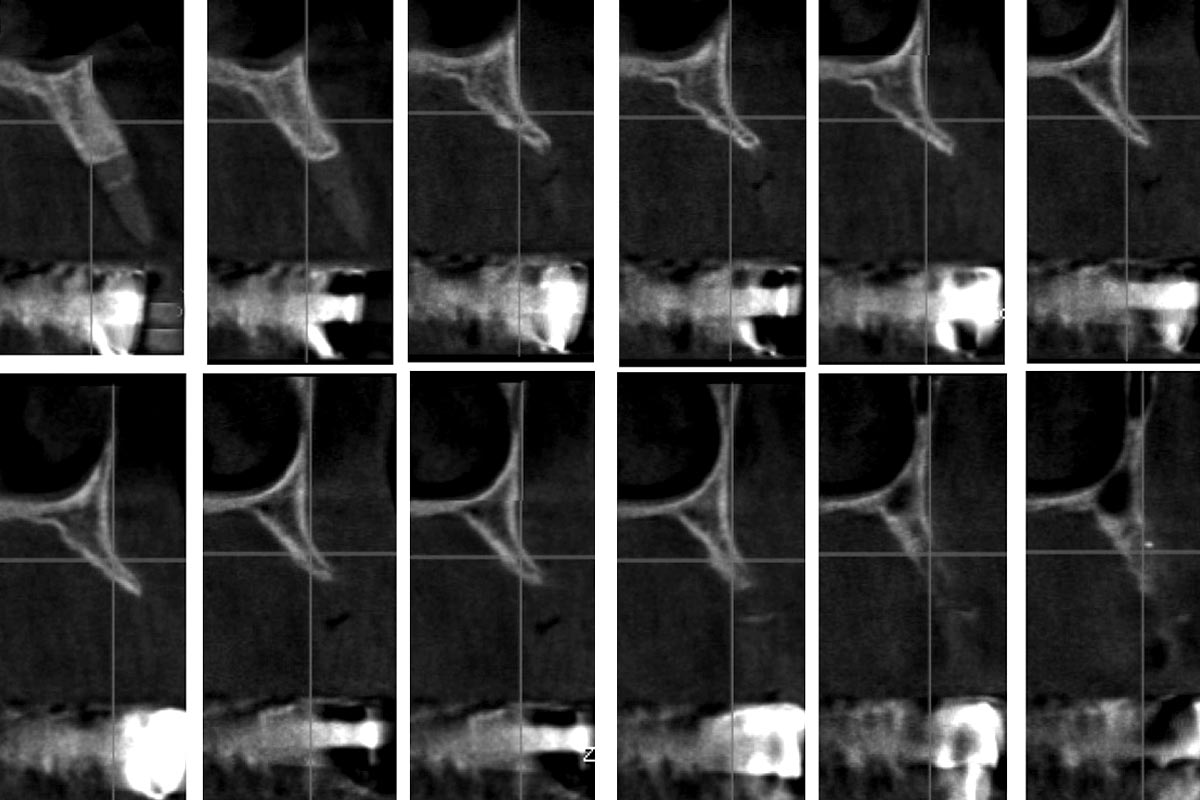

15/16 - 5 years follow up

Reconstruction of Anterior Maxilla with maxgraft® bonebuilder – Dr. B. Han